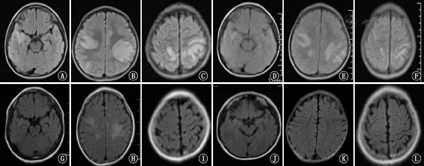

47例ADEM患儿头颅MRI检查显示异常病灶呈多发、不对称的斑片状或大片状信号影(图1)。33例进行了脊髓MRI检查,7例异常,病灶主要位于颈、胸髓内,表现为连续的或节段性长条形信号,T2WI呈高信号,T1WI呈低信号,信号多较均匀,脊髓无增粗,病灶分布见表1。在随访MRI过程中,15 d时所有患儿MRI显示病灶较前缩小,颅内多发病灶完全消失4例(8.51%);1个月时病灶完全消失13例(27.66%);3个月时病灶完全消失23例(48.94%);6个月时病灶完全消失32例(68.09%);1年时病灶完全消失43例(91.49%),余4例(8.51%)有后遗病灶,未发现新病灶出现。

The first cranial admission and the follow-up brain magnetic resonance imaging findings of children with ADEM

注:ADEM:急性播散性脑脊髓炎;FLAIR:液体衰减反转恢复序列成像;入院时轴位FLAIR示大脑半球右颞区(A),半卵圆区(B),双侧顶、枕区(C)高信号;发病15 d轴位FLAIR示右颞区(D),半卵圆区(E),双侧顶、枕区(F)病灶大小及范围缩小;发病6个月轴位FLAIR示右颞区(G),半卵圆区(H),双侧顶、枕区(I)病灶范围明显缩小;发病12个月轴位FLAIR示右颞区(J),半卵圆区(K),双侧顶、枕区(L)病灶完全消失

ADEM:acute disseminated encephalomyelitis;FLAIR:fluid attenuated inversion recovery imaging;high signals in the axial position FLAIR in the region of the cerebral hemisphere right temporal region (A),semi-oval region (B),bilateral top,and occipital area (C);the axial position FLAIR reexamination 15 days after onset showed that the size and extent of the lesions in the right temporal region (D),the semi-oval region (E),and bilateral parietal and occipital region (F) were reduced;the axial position FLAIR reexamination at 6 months after onset showed that the size of the lesions in the right temporal region (G),the semi-oval region (H),and bilateral parietal and occipital region (I) were obviously reduced; the axial position FLAIR reexamination at 12 months after onset showed that the lesions in the right temporal region (J),the semi-oval region (K),as well as bilateral parietal and occipital region (L) disappeared completely

ADEM患儿临床表现的恢复往往早于神经影像学病灶的消退,70%的患者病灶可在数月内完全恢复,少部分可长期遗留病灶,但随访中很少发现有新病灶,若出现新的病灶强烈提示多发性硬化[7,11]。在随访本组47例患儿头颅MRI过程中,15 d时所有患儿头颅MRI病灶较前缩小,病灶完全消失4例(8.51%);1个月时病灶完全消失13例(27.66%);3个月时病灶完全消失23例(48.94%);6个月时病灶完全消失32例(68.09%);1年时病灶完全消失43例(91.94%),余4例(8.51%)有后遗病灶。本组33例同时进行了脊髓MRI检查,其中异常7例,发病6个月随访时脊髓MRI病灶已完全消失,说明ADEM患儿头颅/脊髓MRI病灶随时间推移,逐渐吸收,预后良好。MRI显示的病灶部位与临床症状、体征具有一致性,除对本病早期诊断有很大帮助外,还可以监测病灶是否反复或出现新的病灶,远期随访具有重要临床指导意义。